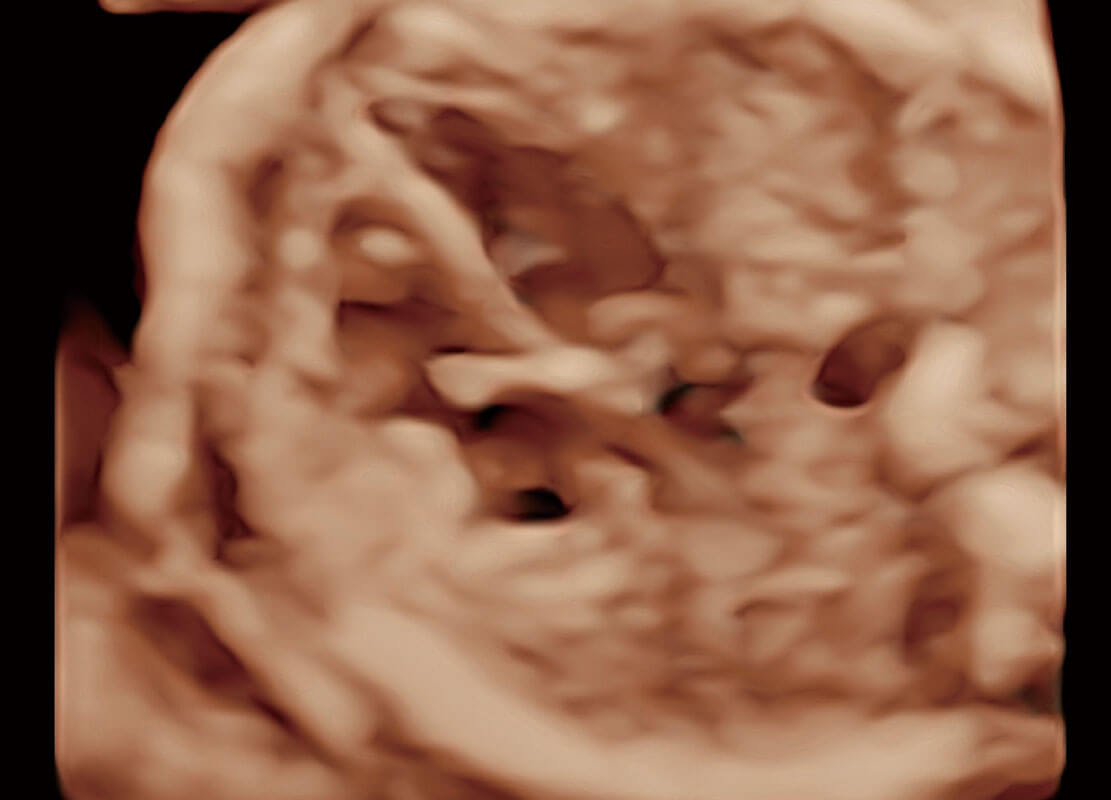

光影成像-孕囊